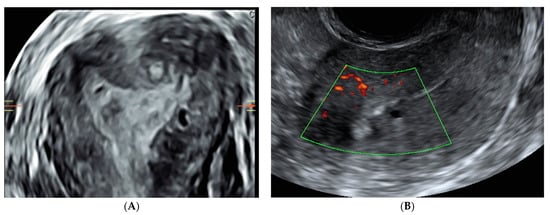

2.1. Ultrasound Diagnosis

- Myometrial cysts and intramyometrial cystic formations of any size (presence of a hyperechogenic halo is not mandatory). The contents could be anechoic, low-level, ground glass or of mixed echogenicity and may be surrounded by a hyperechogenic rim. Doppler can be used for differential diagnosis between blood vessels and myometrial cysts;

- Hyperechogenic islands with intramyometrial hyperechogenic areas within the myometrium that have no connection with the endometrium (regular, irregular, or ill-defined);

- Echogenic subendometrial lines and buds with hyperechogenic subendometrial lines or buds perpendicular to the endometrial cavity in a continuum with the endometrium, disrupting the junctional zone (JZ). On the other hand, the diagnosis of adenomyosis remains uncertain in cases of the presence of only indirect signs, including uterine wall asymmetry, translesional vascularity, JZ changes, fan-shaped shadowing, and globular uterus (Table 1).

- Irregular JZ with a poorly distinguishable endometrial–myometrial border;

- Disrupted JZ, possibly caused by focal or diffuse infiltration of the JZ by endometrial tissue. Uterine contractions may also give rise to apparent irregularities of the JZ or affect wall thickness;

- Alterations of the JZ due to subendometrial hyperechogenic lines and buds, ultrasound signs of focal adenomyosis infiltrating the JZ [26].